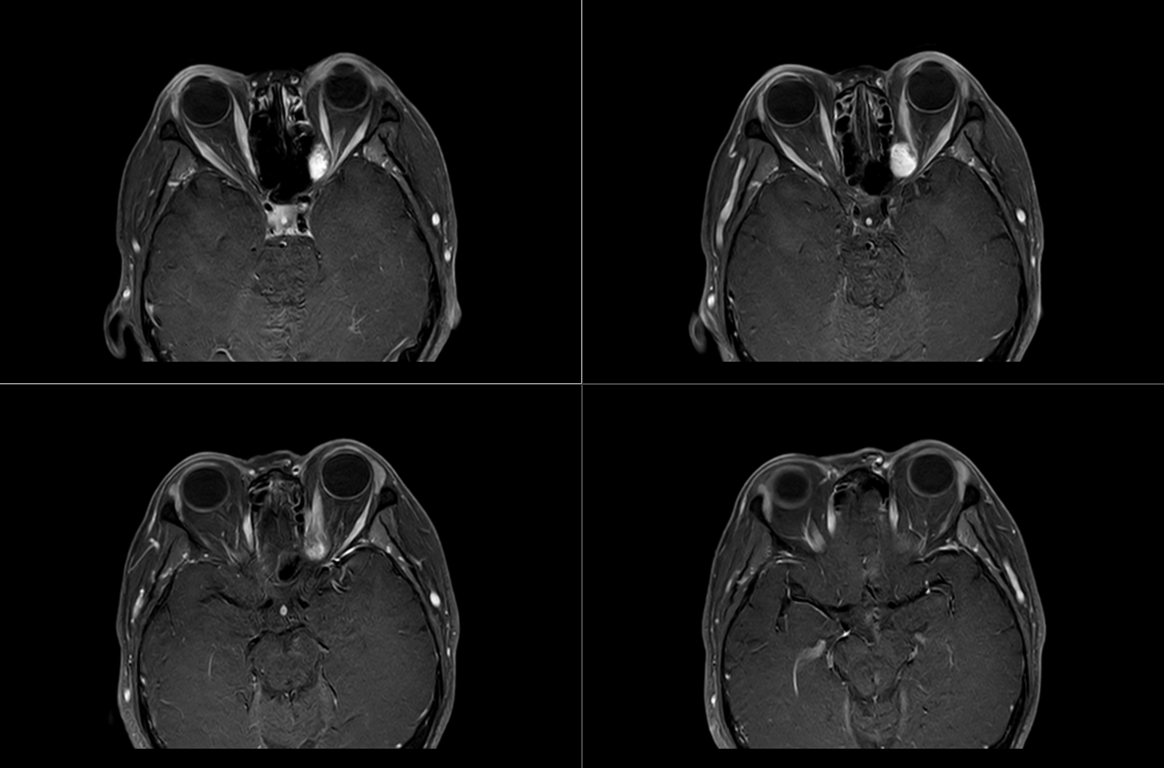

术后影像:

术后影像: